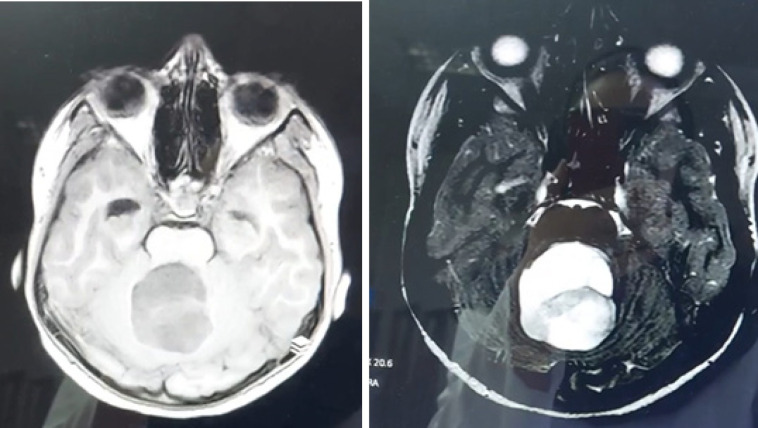

Materials & methods: This retrospective cross-sectional study was conducted on all pediatric patients with posterior fossa tumors admitted to teaching hospitals affiliated with Isfahan University of Medical Sciences from 2017 to 2022. Forty-three patients with posterior fossa tumors were identified, and seven patients were excluded due to diagnoses other than medulloblastoma or ependymoma. Tumor morphology on MRI, tumor density on CT scan, and apparent diffusion coefficient (ADC) values were assessed to differentiate medulloblastoma from ependymoma.

Results: Histopathologic diagnosis was medulloblastoma in 21 patients (60%) and ependymoma in 14 patients (40%). Mean ADC values in medulloblastoma and ependymoma cases were 0.67±0.19 (range= 0.50-1.25) and 1.22±0.29 (range=0.67-1.72), showing a significant statistical difference between the two groups (p-value=0.000). The ADC cut-off point of 0.9825 was associated with 90% sensitivity and 92.9% specificity for differentiation of ependymoma from medulloblastoma.

Conclusion: While tumor morphology on MRI and other studied parameters are unreliable for differentiating medulloblastoma and ependymoma, ADC values may provide a potential diagnostic tool. Further studies are needed to confirm the utility of DWI and other advanced MRI techniques in differentiating these tumors.